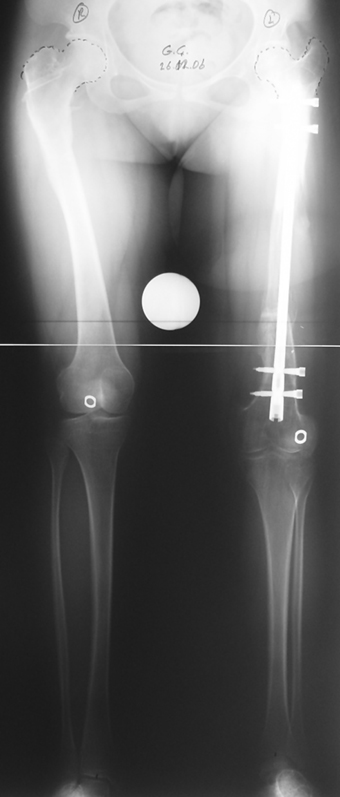

Many patients don’t want to use a shoe support thicker than 2 cm. For length differences between 2 cm and 5 cm, shortening may be considered for tall patients. This can be performed in growing children with a small, minimally invasive, uncomplicated procedure called epiphysiodesis. This means surgical disruption of one or more growth plates. There is a growth plate at the ends of femur, tibia and fibula; this procedure does not halt all growing of the leg. The growing of the longer leg is calculated and halted to allow the shorter leg to catch up.If the procedure is performed at a too early or too late age, the correction may be too much or too little, respectively. Hence, it is important to accurately calculate the most appropriate age for epiphysiodesis. When and at which bone segment epiphysiodesis will be performed shall be calculated by the doctor using different methods such as Gren-Anderson diagram, Moseley curve or Paley’s multiplier method.Epiphysiodesis is not an option for adults because growth plates ar closed. In adults, a bone segment has to be excised surgically in order to shorten the leg. This is usually performed at femur and bone is later fixed with an intramedullary nail. The biggest advantage of this system is that it acutely provides limb length equality for discrepancies less than 5 cm. The common disadvantage of epiphysiodesis and shortening is the shortening of total height of the patient. Because we don’t advice shortening more than 5 cm, height loss can’t be more than 5 cm. For patients who don’t want an epiphysiodesis or shortening operation for length inequalities less than 5 cm, limb lengthening can be preferred in order to equalize the length difference.This can be combined with epiphysiodesis and shortening to decrease a need for another lengthening operation or to decrease the lengthening amount required.